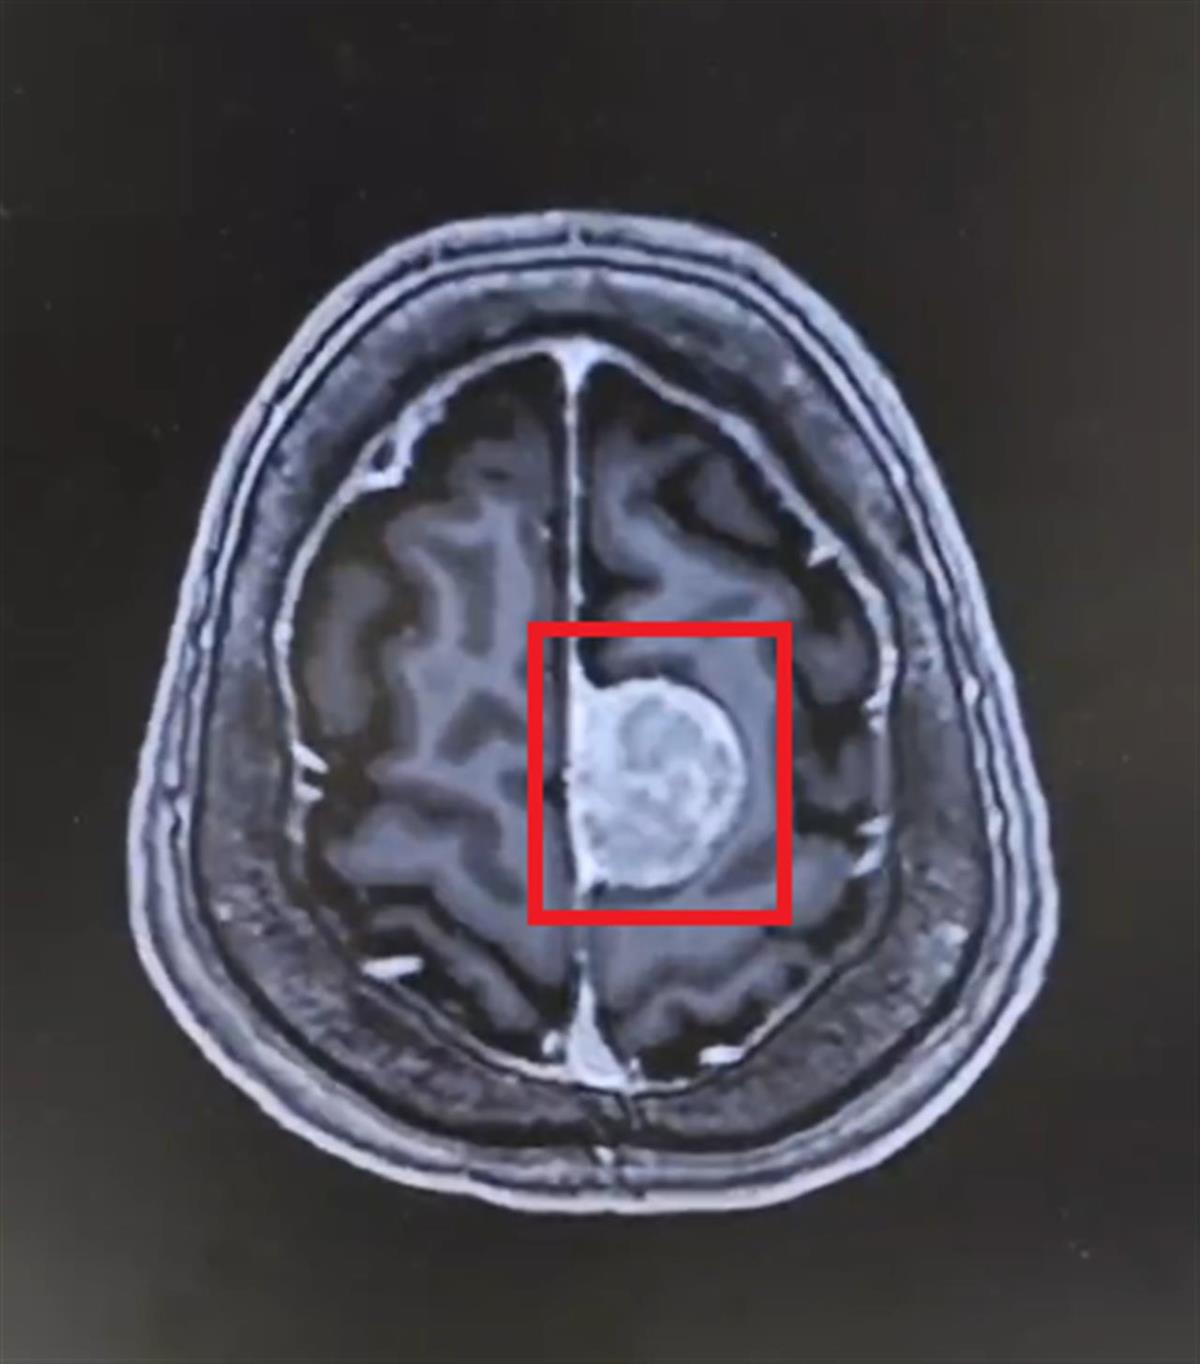

患者颅内肿瘤(通讯员供图)

入院后,经过详细检查和专科评估,结合患者病史和检查结果,泰康神经医学中心团队考虑患者为左侧额部脑膜瘤病变可能。由于病变位于功能区附近,稍有不慎就会引发神经功能障碍,手术难度与风险均较大。针对患者病情,陈劲草教授与泰康同济神经外科赵斌杰主任团队为其制定了周密的手术方案,并于2024年12月9日为患者实施了额叶病损切除术。